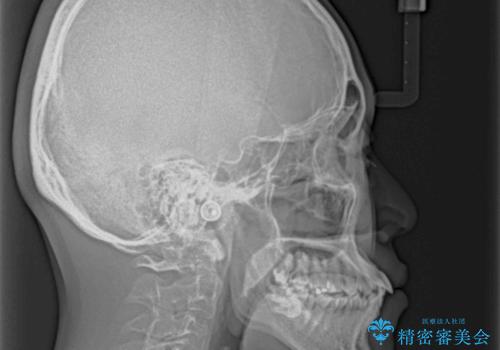

- 全体的なデコボコと、前歯の前に出ている感じを気にして来院された患者様です。

患者様と相談の上、非抜歯にてインビザラインを用いて矯正治療を行うこととし、IPR(歯と歯の間)並びに歯列全体の後方移動により口元の突出感の改善することとしました。